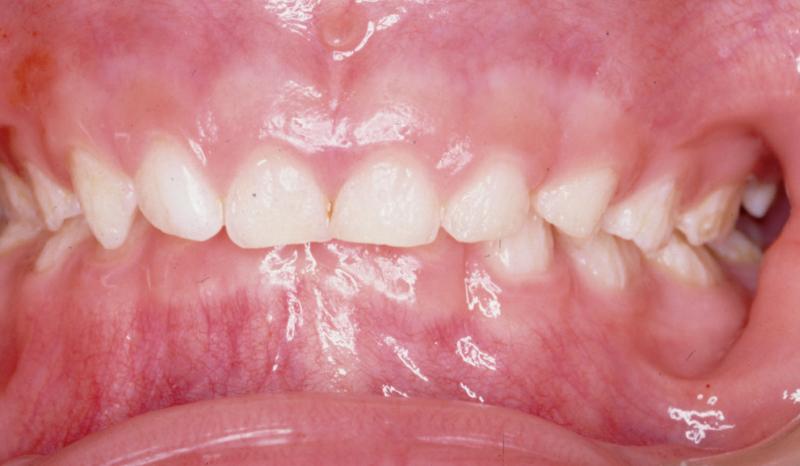

Bilateral talon cusps on the permanent maxillary right and left central incisors AEtalon1 (courtesy of Dr. BM Cleghorn, Dalhousie University) |